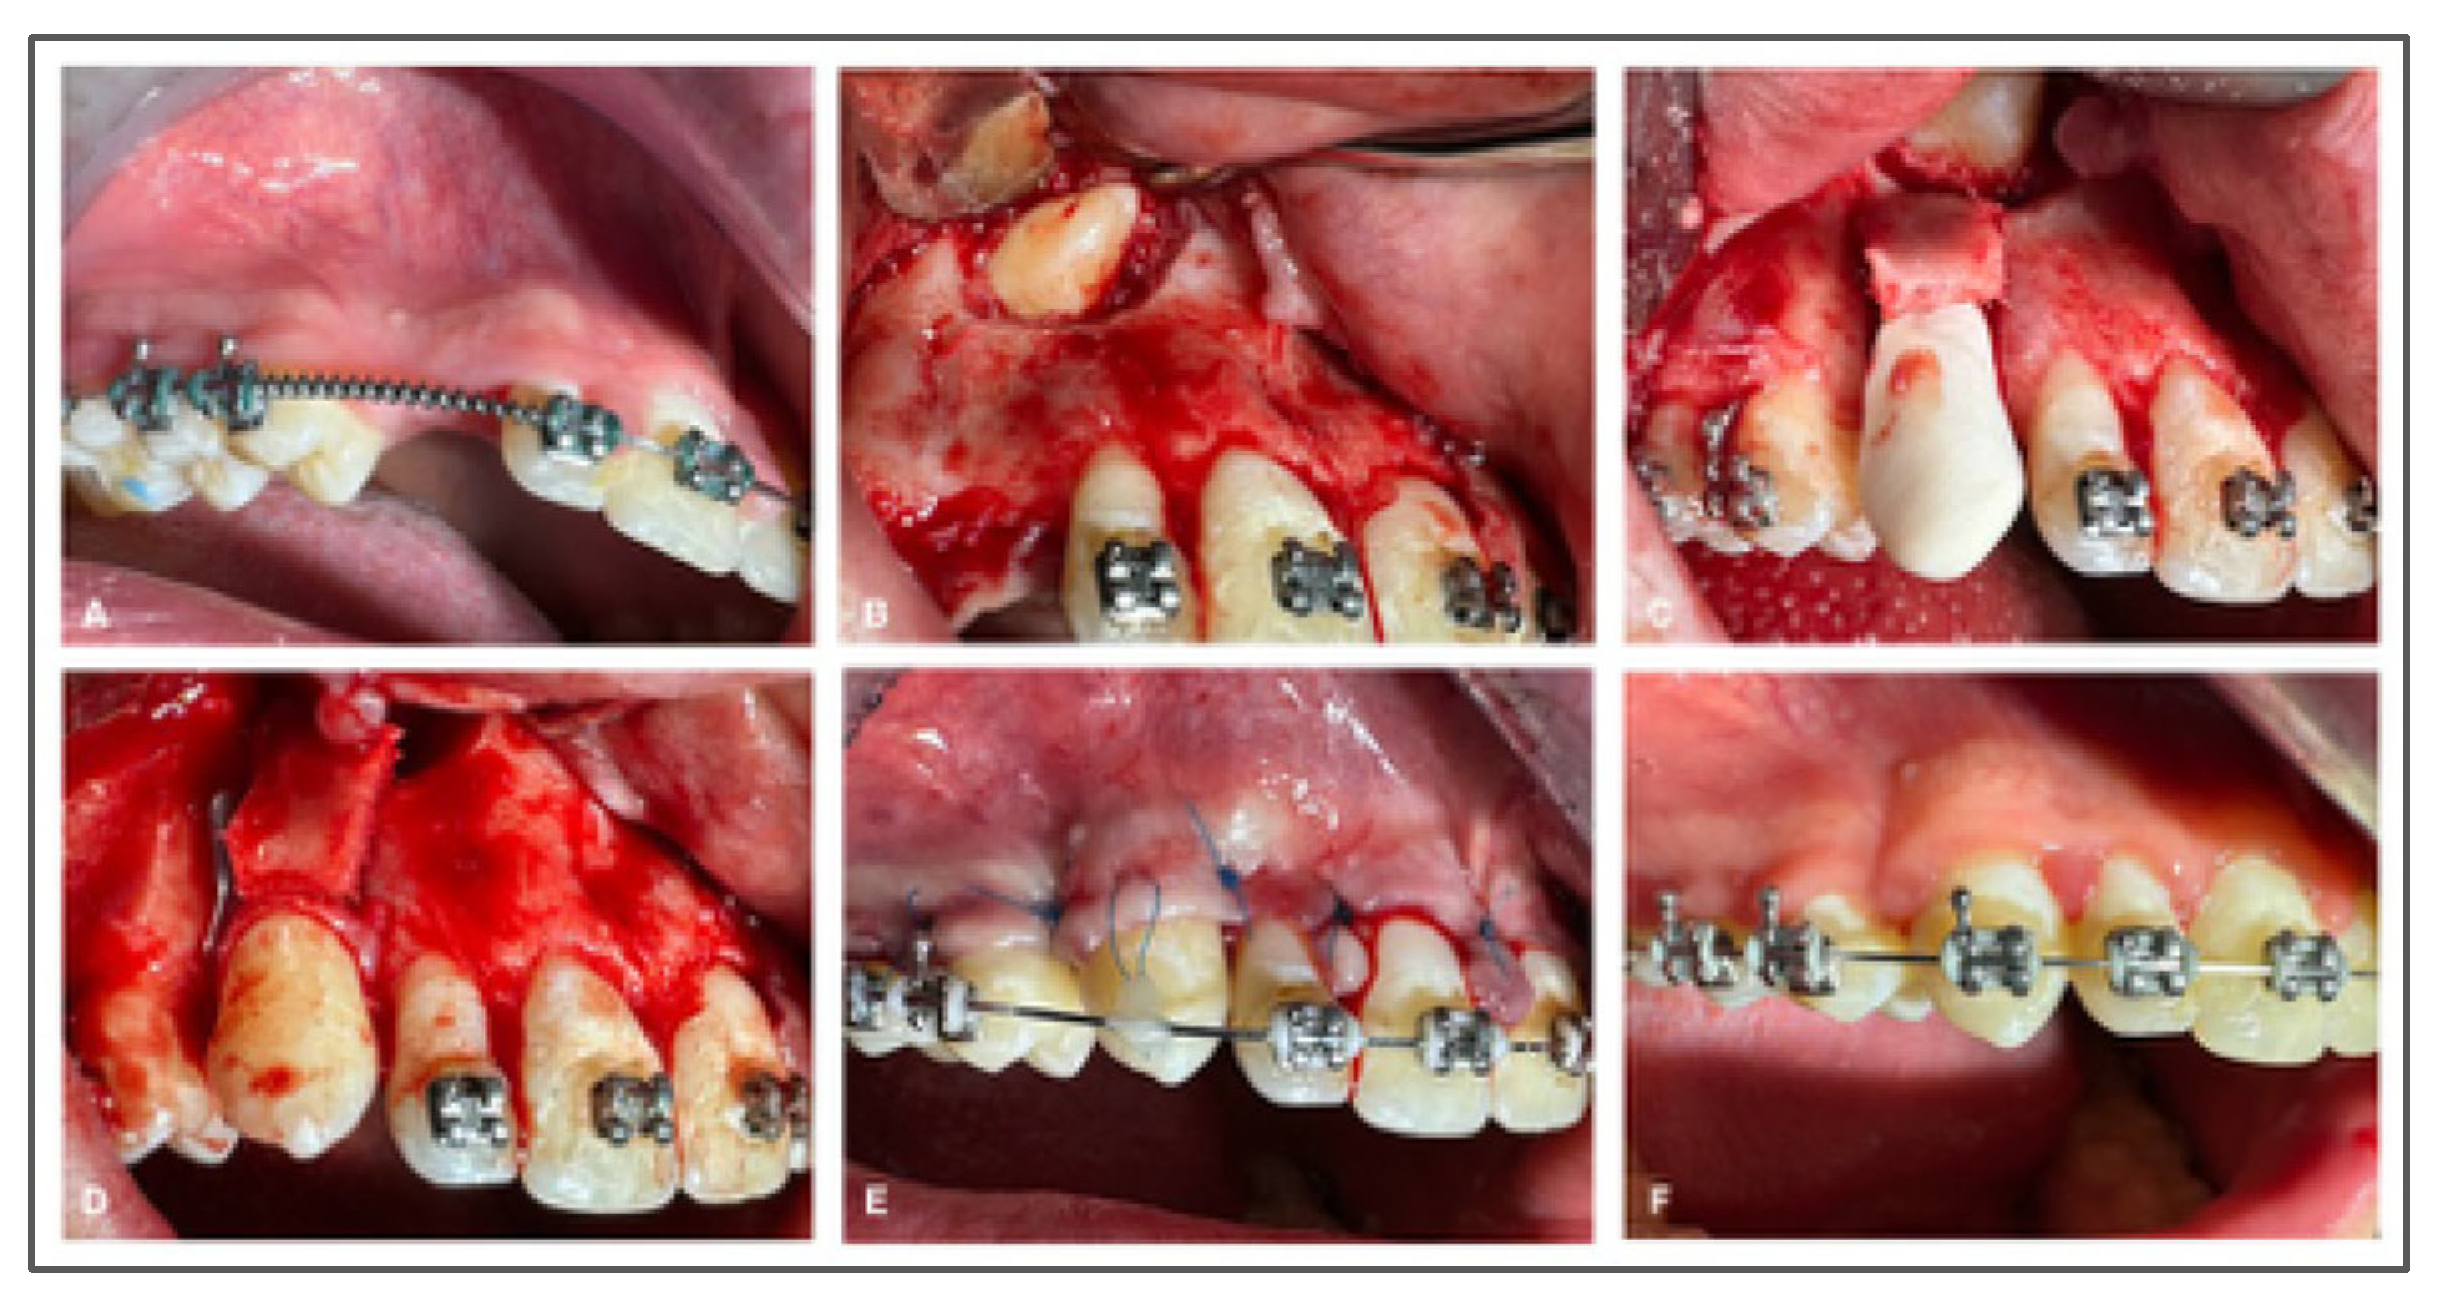

- Explantation: A gentle explantation is mandatory, avoiding PDL damage; an orthodontic pre-treatment should be performed to simplify the procedure because it causes tooth mobility.

- Tooth Repositioning and Splinting: The tooth is reinserted into the socket with minimal pressure and stabilized using a semi-rigid splint. It is crucial that the splint permits slight physiological mobility and does not exert tension on the tooth, which could disrupt reattachment. The recommended duration of splinting varies:

- One week, as per Andreasen’s protocol.

- Two–three weeks according to Tsukiboshi’s guidelines.

During this period, pulp vitality and signs of healing are closely monitored. - 4.

- Gingival Suturing: Soft tissue margins are approximated and sutured to reestablish mucogingival continuity and protect the surgical site.

- Post-Operative Radiography: A periapical radiograph is obtained immediately after reimplantation to confirm accurate repositioning and stabilization.